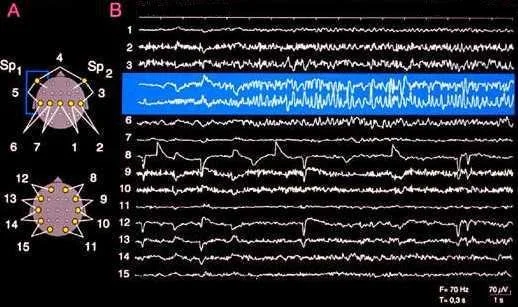

Beispielbild einer EEG-Ableitung

Im folgenden Bild sehen Sie einen Anfall mit Beginn im rechten Temporallappen (Schläffenlappen). Die Registrierung erfolgte mit intrakraniellen Subduralelektroden.

Im nächsten Bild erfolgte die Aufzeichnung eines Anfalls im Oberflächen-EEG mit Beginn links temporal. Die Registrierung erfolgte mit Sphenoidal-Elektroden.